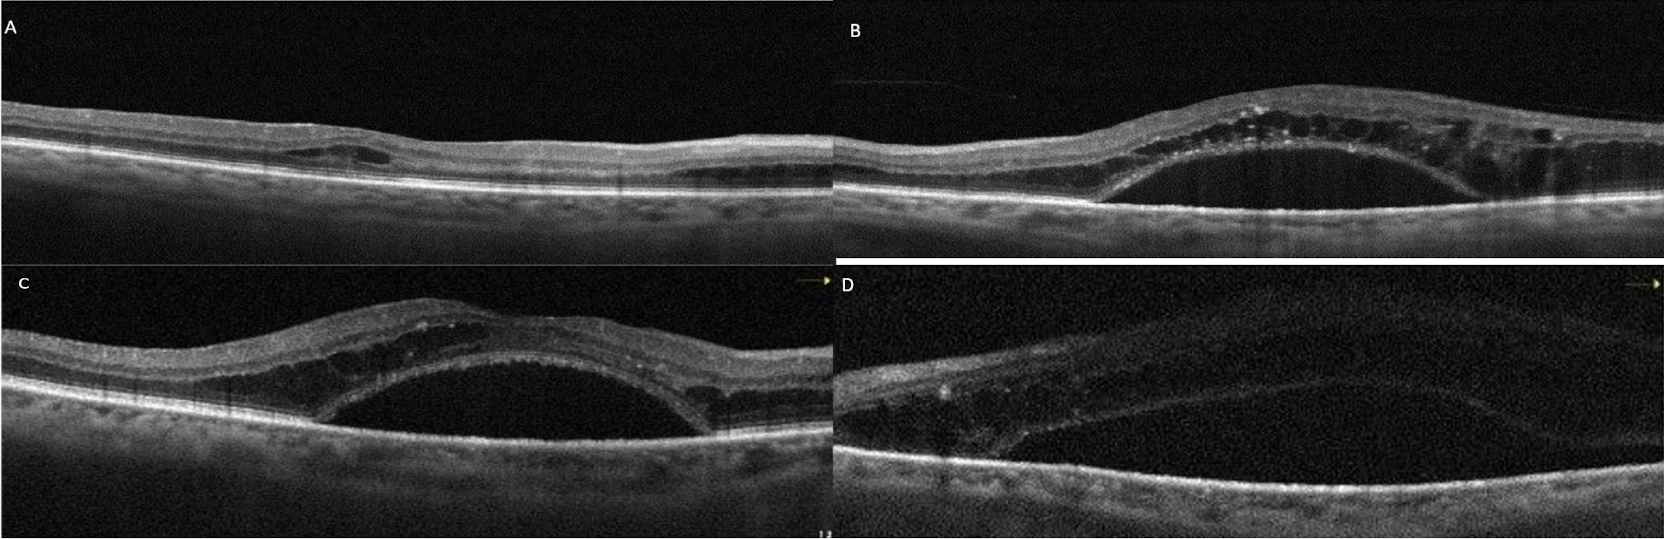

At the patient’s first week follow-up after phacoemulsification surgery, the BCVA of the left eye showed no improvement. Macular OCT images revealed intraretinal and subretinal serous fluid accumulation (Figure 4A and B [Fig. 4]). At that time, laboratory tests showed a hemoglobulin A1c level of 12.1% (reference range: 3.5–6.7%), and a hemoglobin level of 13.6 g/dl (reference range: 12.6–17.4 g/dl). Due to DME, the patient was administered three monthly bilateral intravitreal bevacizumab injections and advised to improve glycemic control. However, the macular edema did not regress; on the contrary, it progressed (Figure 4C and D [Fig. 4]). Subsequently, the patient was lost to follow-up. One year later, ophthalmological examination revealed a BCVA of 20/200 in the right eye and counting fingers at 1 m in the left eye. Slit-lamp examination revealed bilateral pseudophakia, with mild posterior subcapsular opacification in the left eye. No signs of rubeosis iridis were observed. IOPs were within normal limits in both eyes. Fundus examination of the right eye disclosed extensive retinal hemorrhage, hard exudates, microaneurysms, and macular thickening. Visualization of the left fundus was not possible; however, ultrasonographic evaluation indicated findings consistent with intravitreal hemorrhage. Upon further assessment, it was revealed that the patient had been diagnosed with MM approximately one month earlier and had since initiated chemotherapy. At that time, the patient’s hemoglobin level was 11.7 g/dL (reference range: 13.2–16.6 g/dL), and hemoglobin A1c was 6.7% (reference range: 3.5–5.7%). The patient was advised to maintain an upright sitting position, and continue the systemic treatment.

Figure 4: Right (A) and left (B) macular OCT images of case 2 at the first week after left cataract surgery. While mild intraretinal edema was present in the right eye, there was marked subretinal serous fluid accumulation accompanied by intraretinal cysts in the left eye. After 3 monthly intravitreal bevacizumab injections, persistant subretinal fluid is visible in the right (C) and the left (D) eye.

Two months later, partial clearance of vitreous hemorrhage was observed (Figure 5A and B [Fig. 5]). Due to the presence of widespread retinal nonperfusion areas on FFA (Figure 5C and D [Fig. 5]), panretinal laser treatment was initiated. At that time, BCVA was 20/200 in the right eye and counting fingers at 2 m in the left eye. OCT demonstrated regression of macular edema in the right eye; however, hard exudates remained prominent, and disruption of the ellipsoid zone was noted (Figure 5E [Fig. 5]). The left eye remained difficult to visualize, although OCT findings suggested some resolution of the edema (Figure 5F [Fig. 5]). Approximately eight months after the initiation of systemic treatment, the hemorrhages in the right eye showed partial regression. Vitreous hemorrhage in the left eye had significantly cleared.